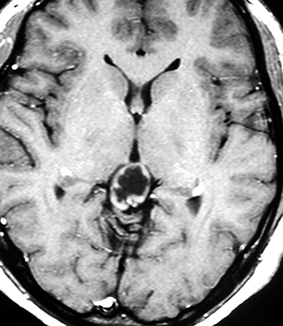

放射線化学療法後の画像です。腫瘍境界は不明瞭(左)で,腫瘍内出血(中央)して,左の視床に浸潤しています。かなりリスクは高いのですが,これを開頭手術で全摘出しました(右),この時点で完全寛解 CR です。この後にさらに化学療法と幹細胞移植(PBSCT,大量化学療法)が加えられました。